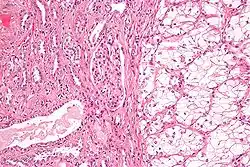

Microscopy

Generally, the cells have a clear cytoplasm, are surrounded by a distinct cell membrane and contain round and uniform nuclei.

Microscopically, CCRCCs are graded by the ISUP/WHO as follows:[1][2]

- Grade 1: Inconspicuous and basophilic nucleoli at magnification of 400 times

- Grade 2: Clearly visible and eosinophilic nucleoli at magnification of 400 times

- Grade 3: Clearly visible nucleoli at magnification of 100 times

- Grade 4: Extreme pleomorphism or rhabdoid and/or sarcomatoid morphology

Clear-cell renal-cell carcinoma. HE, × 100

Clear-cell renal-cell carcinoma. HE, × 100 -